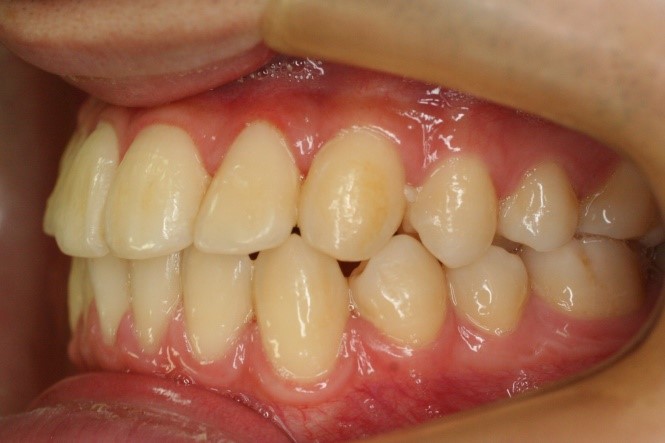

• 右側